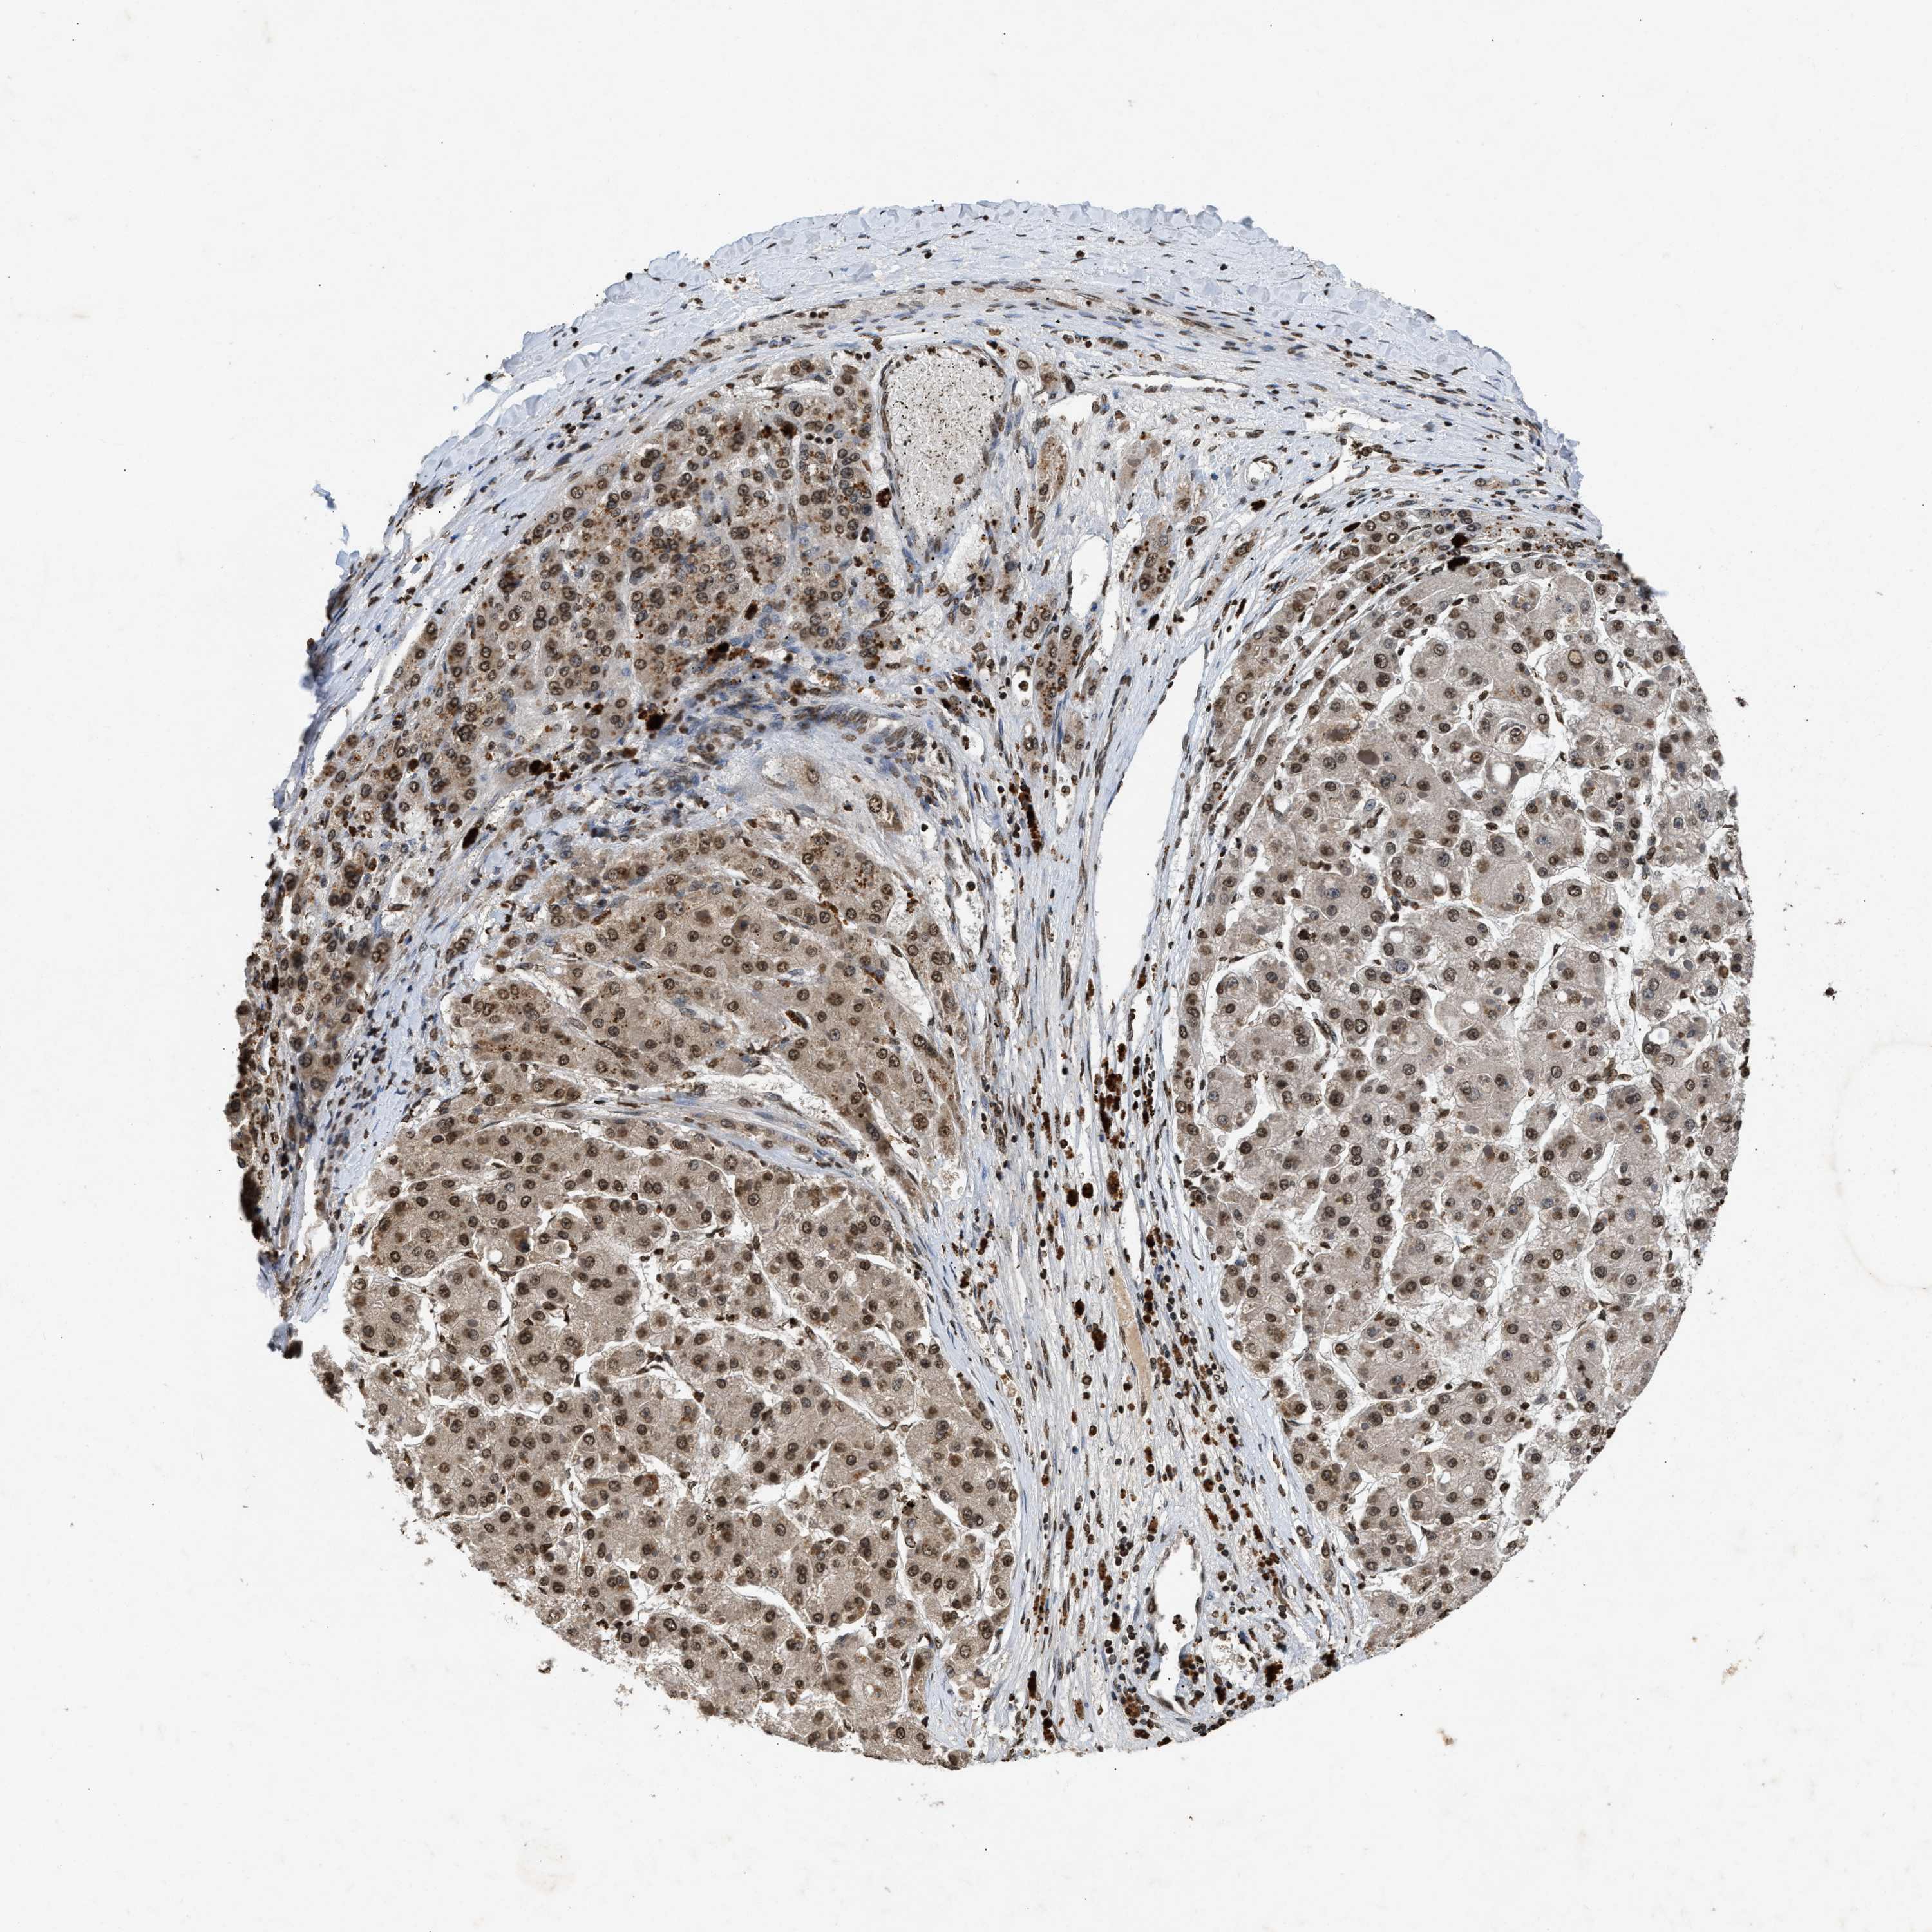

LIVER CANCER - Protein expressioni

A mouse-over function shows sample information and annotation data. Click on an image to view it in a full screen mode. Samples can be filtered based on level of antibody staining by selecting one or several of the following categories: high, medium, low and not detected. The assay and annotation is described here.

Note that samples used for immunohistochemistry by the Human Protein Atlas do not correspond to samples in the TCGA dataset.

Antibody stainingi

Antibody staining in the annotated cell types in the current human tissue is reported as not detected, low, medium, or high, based on conventional immunohistochemistry profiling in selected tissues. This score is based on the combination of the staining intensity and fraction of stained cells.

Each image is clickable and will lead to virtual microscopy that enables deeper exploration of all samples and also displays staining intensity scores, fraction scores and subcellular localization as well as patient and tissue information for each sample.

Antibody HPA019955

Staining

High

Medium

Low

Not detected

Intensity

Strong

Moderate

Weak

Negative

Quantity

>75%

75%-25%

<25%

None

Location

Nuclear

Cytoplasmic/membranous

Cytoplasmic/membranous,nuclear

Cholangiocarcinoma

Carcinoma, Hepatocellular, NOS